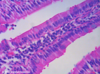

3

Q

A

simple columnar epithelium